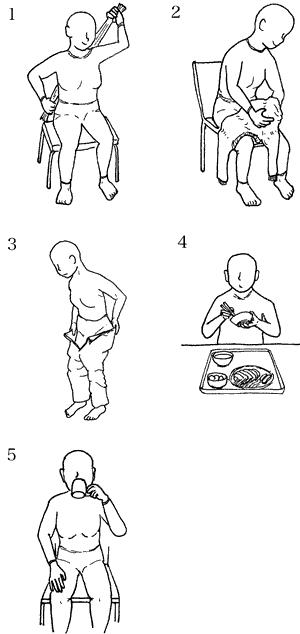

56歳の女性。脳梗塞による左片麻痺。Brunnstrom法ステージは左上肢Ⅲ、左手指Ⅲ、左下肢V。この患者で実用的にできる動作はどれか。

1

1

2

2

3

3

4

4

5

5

63歳の男性。脳出血による左片麻痺。Brunnstrom法ステージは左上肢Ⅲ、左手指Ⅲ及び左下肢Ⅳ。上肢の分離運動促通を目的とした自主訓練として適切なのはどれか。

1

1

2

2

3

3

4

4

5

5

56歳の男性。左片麻痺。脳梗塞発症後3 か月経過。ブルンストローム法ステージは上肢III、手指III、下肢IV。認知や感覚に問題はない。この患者の動作指導で適切でないのはどれか。

1

寝返りでの肩甲帯の前方突出と肩関節内転

2

前開きシャツの袖通しでの肘伸展

3

ファスナー開閉での母指と示指での側腹つまみ

4

食事中のテーブル上での上肢保持

5

小物入れ保持での肩内旋・肘屈曲

50代の女性。脳出血による右片麻痺。発症後8か月が経過した。右利きであったが利き手交換を実施した。Brunnstrom法ステージは上肢Ⅳ、手指Ⅳ、下肢Ⅴ、感覚機能は表在・深部とも軽度鈍麻で、握力は右2 kg、左28 kg、立位バランスは良好である。この患者が実施可能な動作はどれか。

1

1

2

2

3

3

4

4

5

5